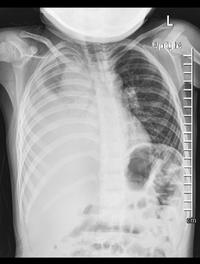

Les épanchements pleuraux et les empyèmes sont les complications principales des pneumonies communautaires de l’enfant. La pleurésie [...]